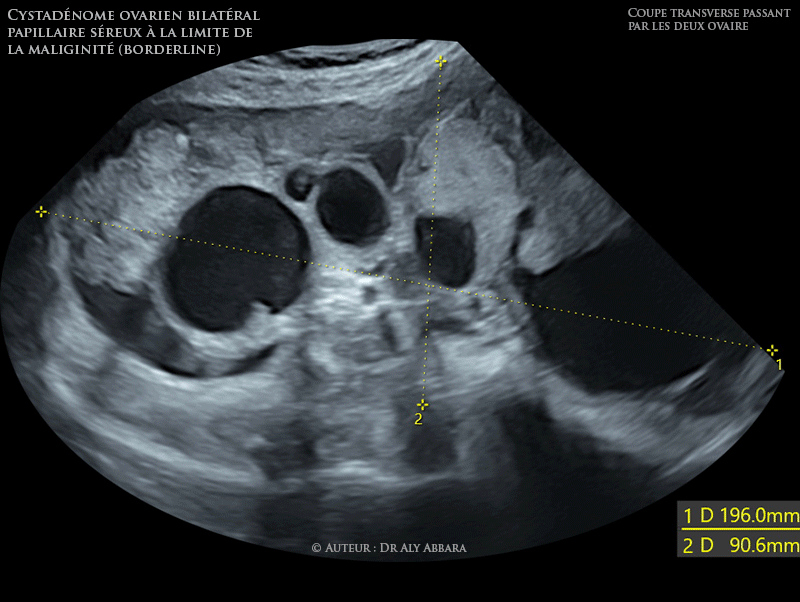

Il s'agit échographiquement d'une volumineuse tumeur ovarienne bilatérale multiloculaire, mixte, comportant de formations solides et d'autres liquidiennes caractérisées par la présence d'importantes végétations endophytiques et parfois exophytiques.

L'ensemble de cette tumeur bilatérale ovarienne forme une masse de 196 mm de large et 90,6 mm de hauteur. La composante ovarienne droite mesure 87 x 66 mm de grande axe, et celle de l'ovaire gauche mesure 110 x 73 x 101 mm.